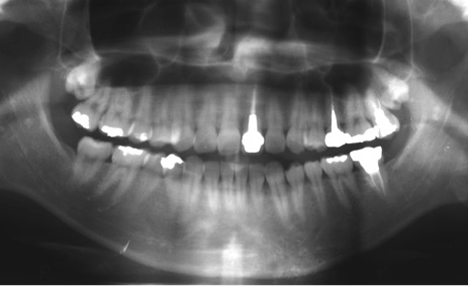

初診で当院を受診したときのレントゲン写真です。

抜歯となった前歯は差し歯の治療がなされていることがわかります。また、差し歯の両隣は天然歯

(何も治療をしていない患者様ご自身の歯)となっています。

インプラント治療が完了してから1年後の定期健診時のレントゲン写真です。治療後の経過は良好で、安定した状態を保っています。